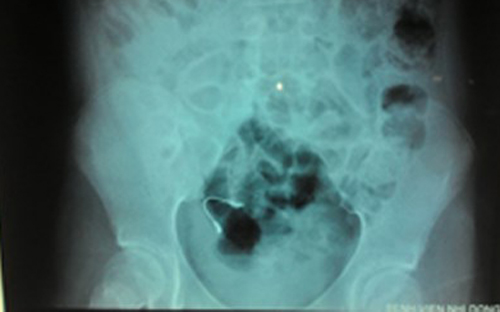

Cọng kẽm niềng răng mà bệnh nhi nuốt vào bụng. Ảnh: BV cung cấp |

Sau khi kiểm tra X-quang, các bác sĩ phát hiện có dị vật ở đường tiêu hóa nên cho bệnh nhi uống thuốc nhuận tràng và theo dõi. 3 ngày sau, bé A. tự đi tiêu ra dị vật, tình trạng sức khỏe trở lại bình thường, không đau bụng, ăn uống tốt và đã được xuất viện.